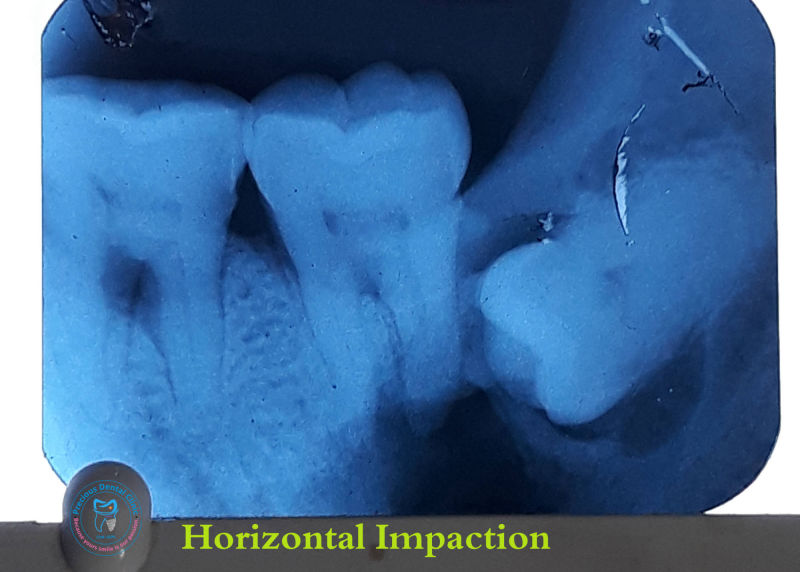

Collection of photos, here you will find the photos of doctor, services, environment and work.